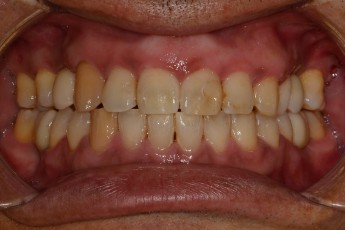

BEFORE & AFTER